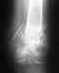

Доброго дня! 15 июня мой ребенок (сын, 8 лет) сломал обе руки (запястья)- катался на роликах. Наложили гипс. 24 июня сделали повторный рентген: на одной руке смещение - смещение в лучевую сторону на 1/3 диаметра кости. Врачи разошлись во мнении: оставить так срастаться или репонировать кость, вставив пластину.

Просим нас проконсультировать. Сын сломал 2 руки: перелом левой и правой лучевой кости. Левая - в порядке, а вот правая - смещение на 1/3 (снимок и выписка во вложении). Местные врачи говорят, что это допустимо по норме, так оставить срастаться. А другой врач сказал, что "во-первых,репонировать кость все равно надо.срастется плохо-будет кисть висеть,рука почти не будет фунциклировать. Пусть просят,чтобы стержень вбили или пластину поставили".Что делать? Решать надо прямо сейчас, така как дни идут. Мы из города Череповца. Нам предлагают съездить на косультацию в Институт Турнера, но сказали о возможности спросить мнение специалистов через сайт.

• Кликните для загрузки файла IMG_20130626_141543.jpg